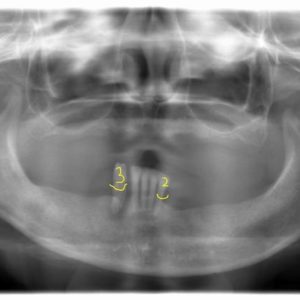

永久歯の本数が少ない先天性欠損歯の治療例

先天性欠損歯とは? 一般的にはあまり知られていませんが、10人に1人くらいの割合で永久歯の本数が通常よりも少ない人がいます。 先天性欠損歯が起こる明確な原因はわかっていませんが、永久歯への生え変わり時期にレントゲン写真を […]